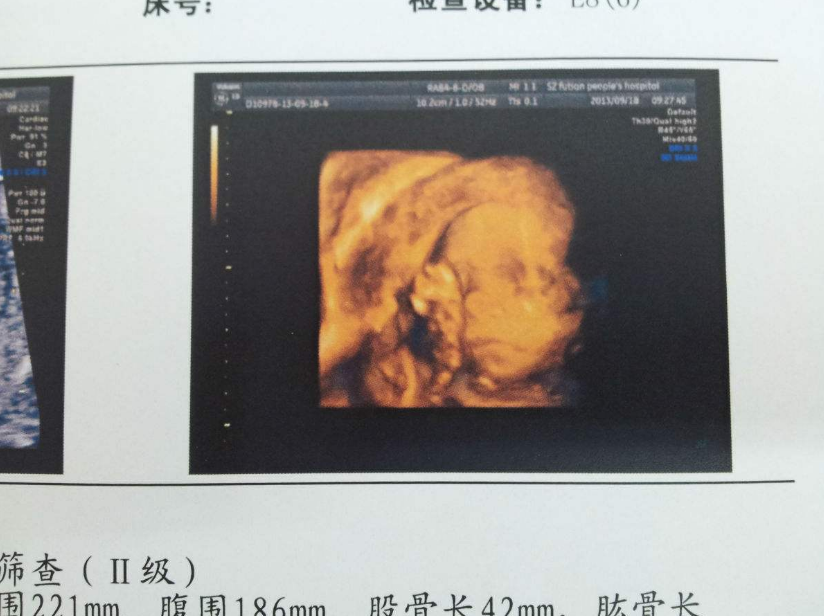

胎寶寶臍帶繞頸,說白了就是臍帶繞到脖子上了。在產科門診十分常見。